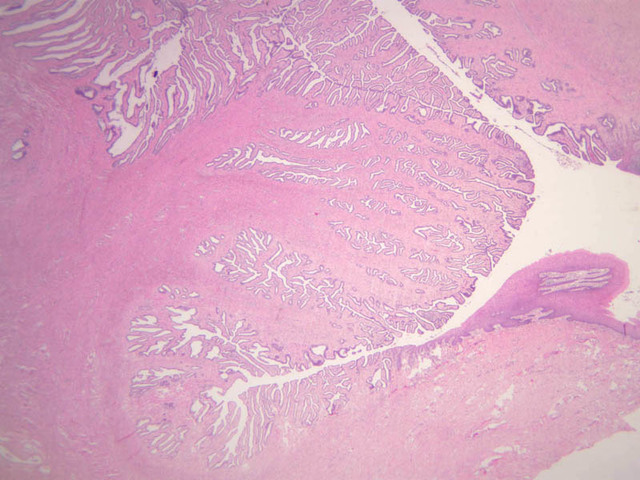

Secretory Phase

This phase occurs on days 15 to 27 and corresponds to the ovarian luteal phase characterized by rising levels of progesterone. The epithelial cells begin to secrete a mucoid fluid rich in nutrients, especially glycogen. The glands become highly coiled and folded and toward the end, very distended. The density of the stroma lessens as it becomes edematous. (slides B-99 [2.5x, 10x, 20x, 40x] [2.5x, 10x, 20x, 40x]; B-100 [1x, 2.5x] [2.5x, 10x, 20x, 40x] [2.5x, 10x, 20x, 40x])